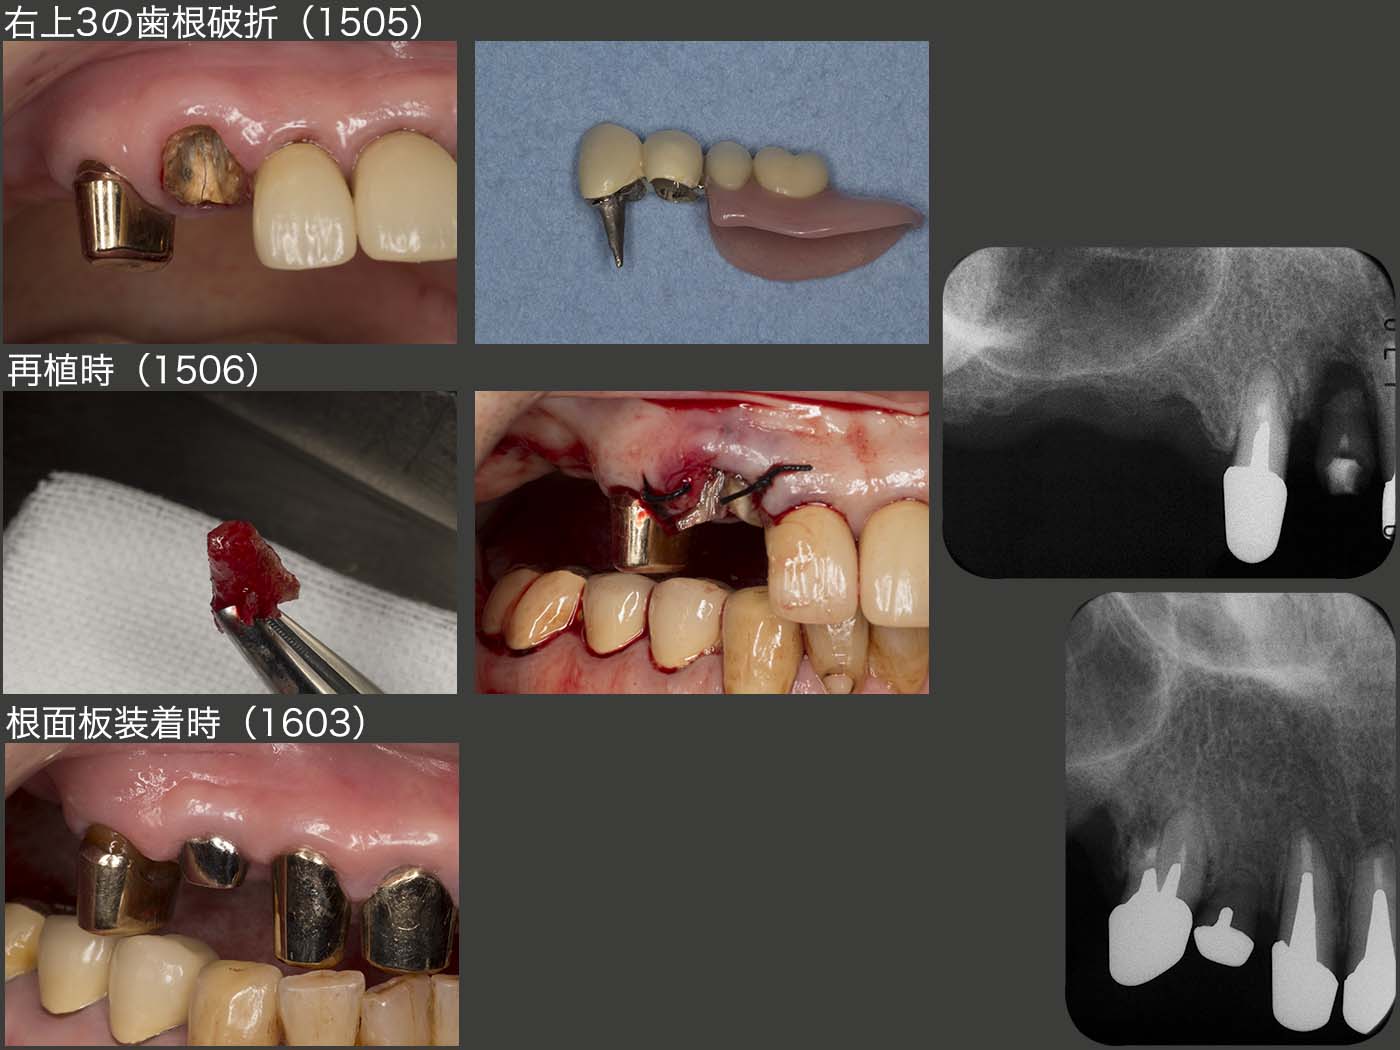

2015年5月,これも恐れていたと言うより予想どおりであるが,右上に問題が生じた.強いて言えば,もう少し年を重ねた先に起こるのでは?また,右上4が先に歯根破折すると思っていた.ところが実際は右上3に歯根破折が生じた.幸い破折線が根尖まで達していなかったので再植することができた.しかし,右上3は支台歯として力,特に水平力を担うには,歯根が短く無理があるため,残りの前歯4本を支台歯として組み込み,上顎の支台歯全てを2次固定し,全体で力に対抗できるようにした.